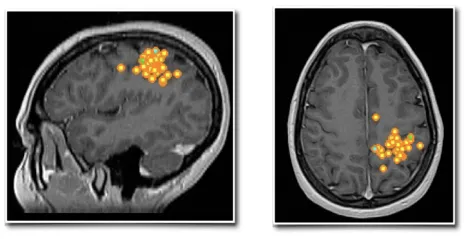

此外,脑磁图进一步在管理躯体感觉的中央后回区域捕捉到了异常的癫痫样放电。下图分别为琳娜在矢状位(左)和轴位(右)上显示的Rolandic区(中央区)棘波簇(黄色点带橙色轮廓)。